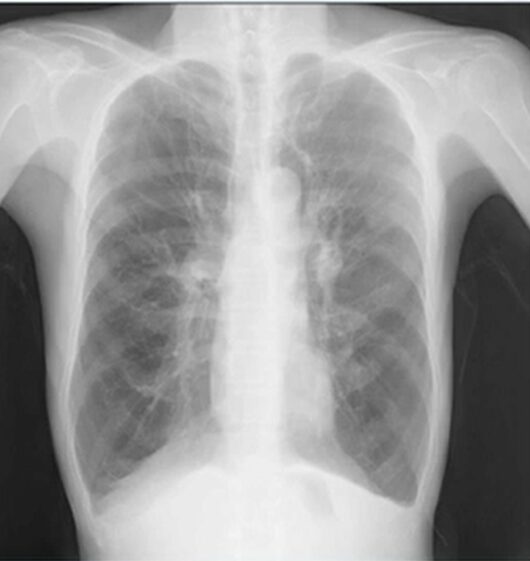

COPDのレントゲン(X-p)写真

典型的なCOPDのレントゲン写真(X-p)です。まずCOPDのレントゲン写真(X-p)の特徴です。

横隔膜の平坦化:

息を吐き出しにくくなり肺に空気が残りやすくなるため、横隔膜が通常よりも下がり、平らになって写ります。

肺の過膨張と樽状胸郭:

肺が常に膨らんだ状態(過膨張)になり、胸郭が通常よりも横に広がった樽のような形(樽状胸郭)に見えることがあります。

肺野が黒く写る(肺気腫):

肺胞が破壊され、X線が通りやすくなることで、肺全体が黒っぽく写ることがあります。

滴状心(心臓が細長く写る):

肺に押されて心臓が縦に引き伸ばされ、細長い形(滴状心)で写ることがあります。

肋間腔(肋骨の間)の開大:

肺の膨張により、肋骨の間隔が広がって見えることがあります。

本症例では、肺が大きく縦長に見えます(通常第10肋骨前後に横隔膜。本症例は数えると12肋骨まで数えられる)。

横隔膜が平らになっています(=横隔膜平定化)。

CPアングル dullで心臓は縦長に伸びている、といった特徴があります。